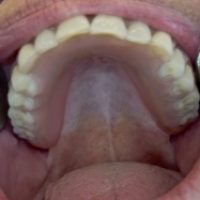

Denne løsning fungerer ved, at der indsættes implantater i kæben, der fungerer som en tryklås. På protesens bund sidder der en trykknap, som ´knappes´ fast på implantatet. Det sikrer, at protesen sidder helt fast i munden, selvom du ikke har egne tænder at sætte den fast på. Drejer det sig om en protese i overmunden, er der desuden den fordel, at din udtale bevares samt følelsen af at smagsoplevelsen bliver bedre , da protesen så kan blive ganefri.